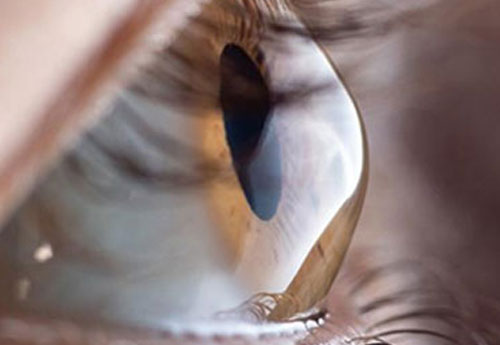

Cornea

The cornea—the clear, dome-shaped front layer of the eye—is crucial for focusing light and...